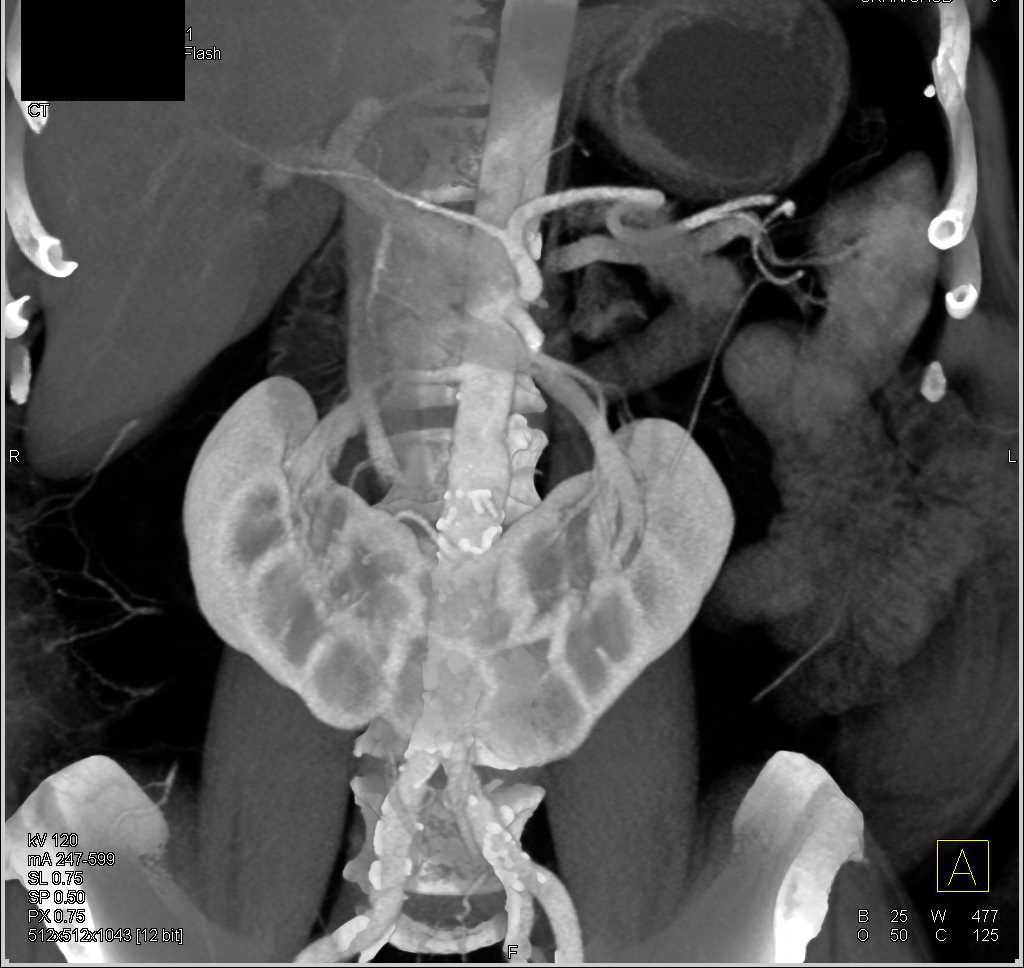

Left Renal Laceration and Contrast Extravasation